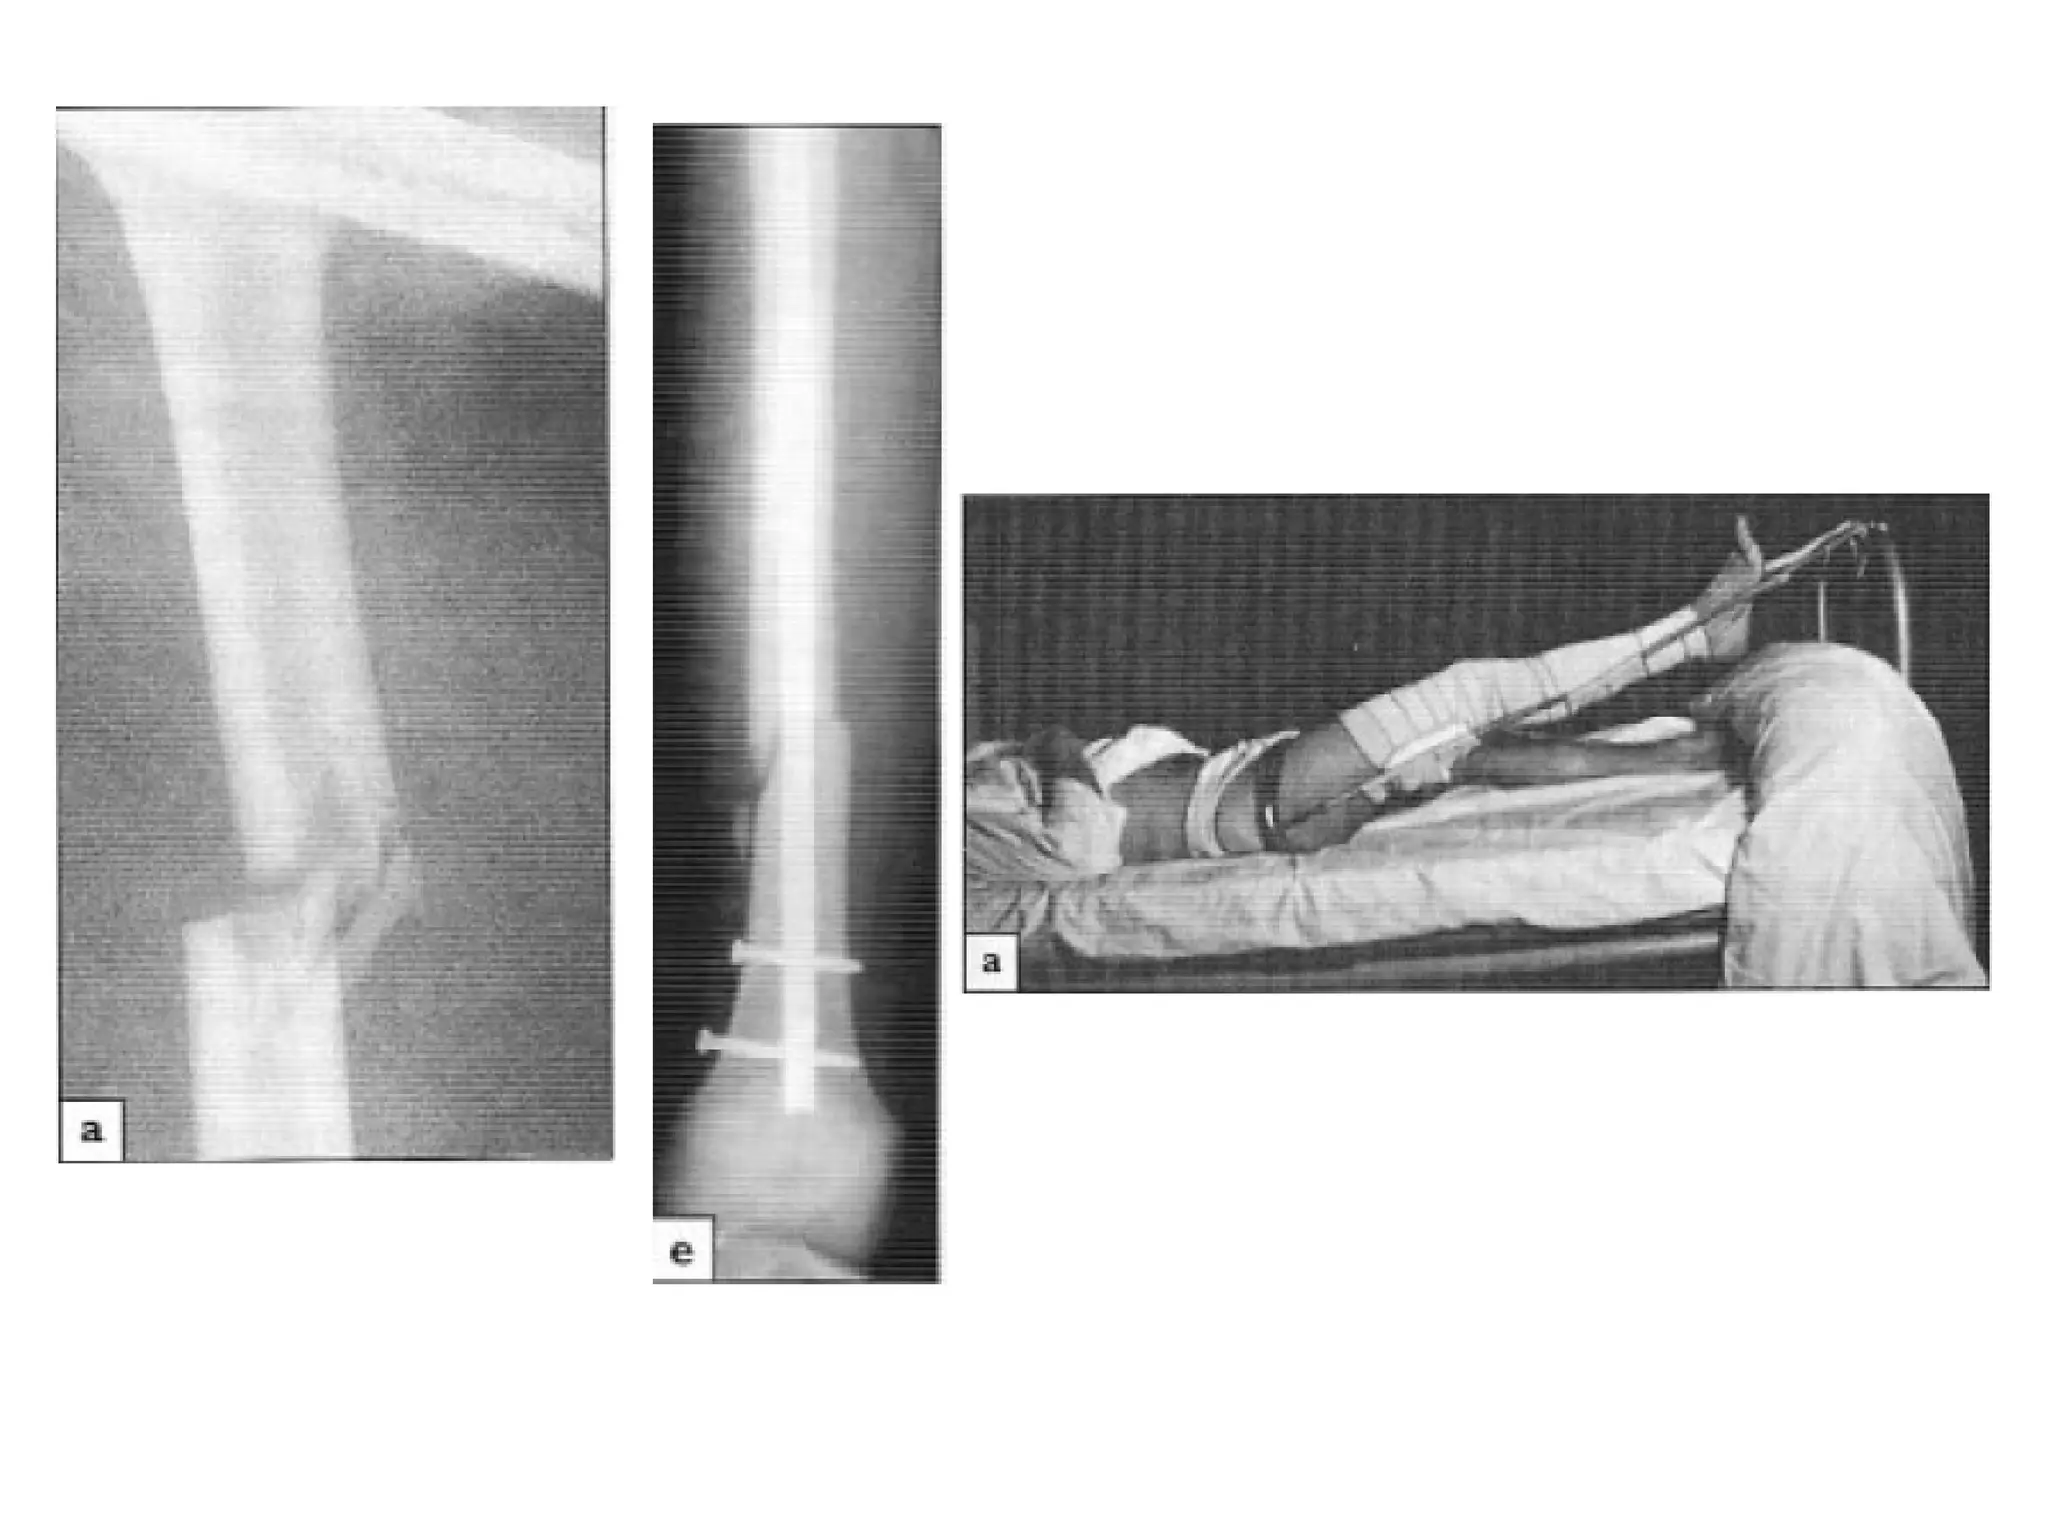

• Emergency treatment:

• Treat the shock

• Transport Splintage of # “Thomas’ splint”

• Once the pt is in the hospital, skin traction can be changed

to skeletal traction if op. treatment is to be delayed or if

non operative treatment is planned

• Adults: Skeletal traction through a pin or tightly strung K

wire behind the tibial tubercle. Traction (8-10 kg) is applied

over pulleys at the foot of the bed .

• Exercises are begun.

• Once the fracture was sticky (8 weeks), traction can be

discontinued and the pt. allowed to up and partial weight

bearing in a cast or a brace (distal #)

traction (through tibia) & splintage

• If the distal fragment is displaced by gastrocnemius pull, a

second pin above the knee and vertical traction

will correct this.